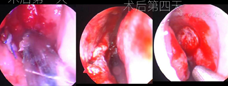

术后情况:患者术后照片见图3。1周拆除鼻中隔缝线,鼻中隔穿孔愈合(图4),术后25 d见图5。鼻底部供区2个月后瘢痕上皮化完成,原有鼻塞、鼻干、涕中带血消失,疗效明显。1年后复诊鼻中隔愈合良好,鼻部症状明显改善。